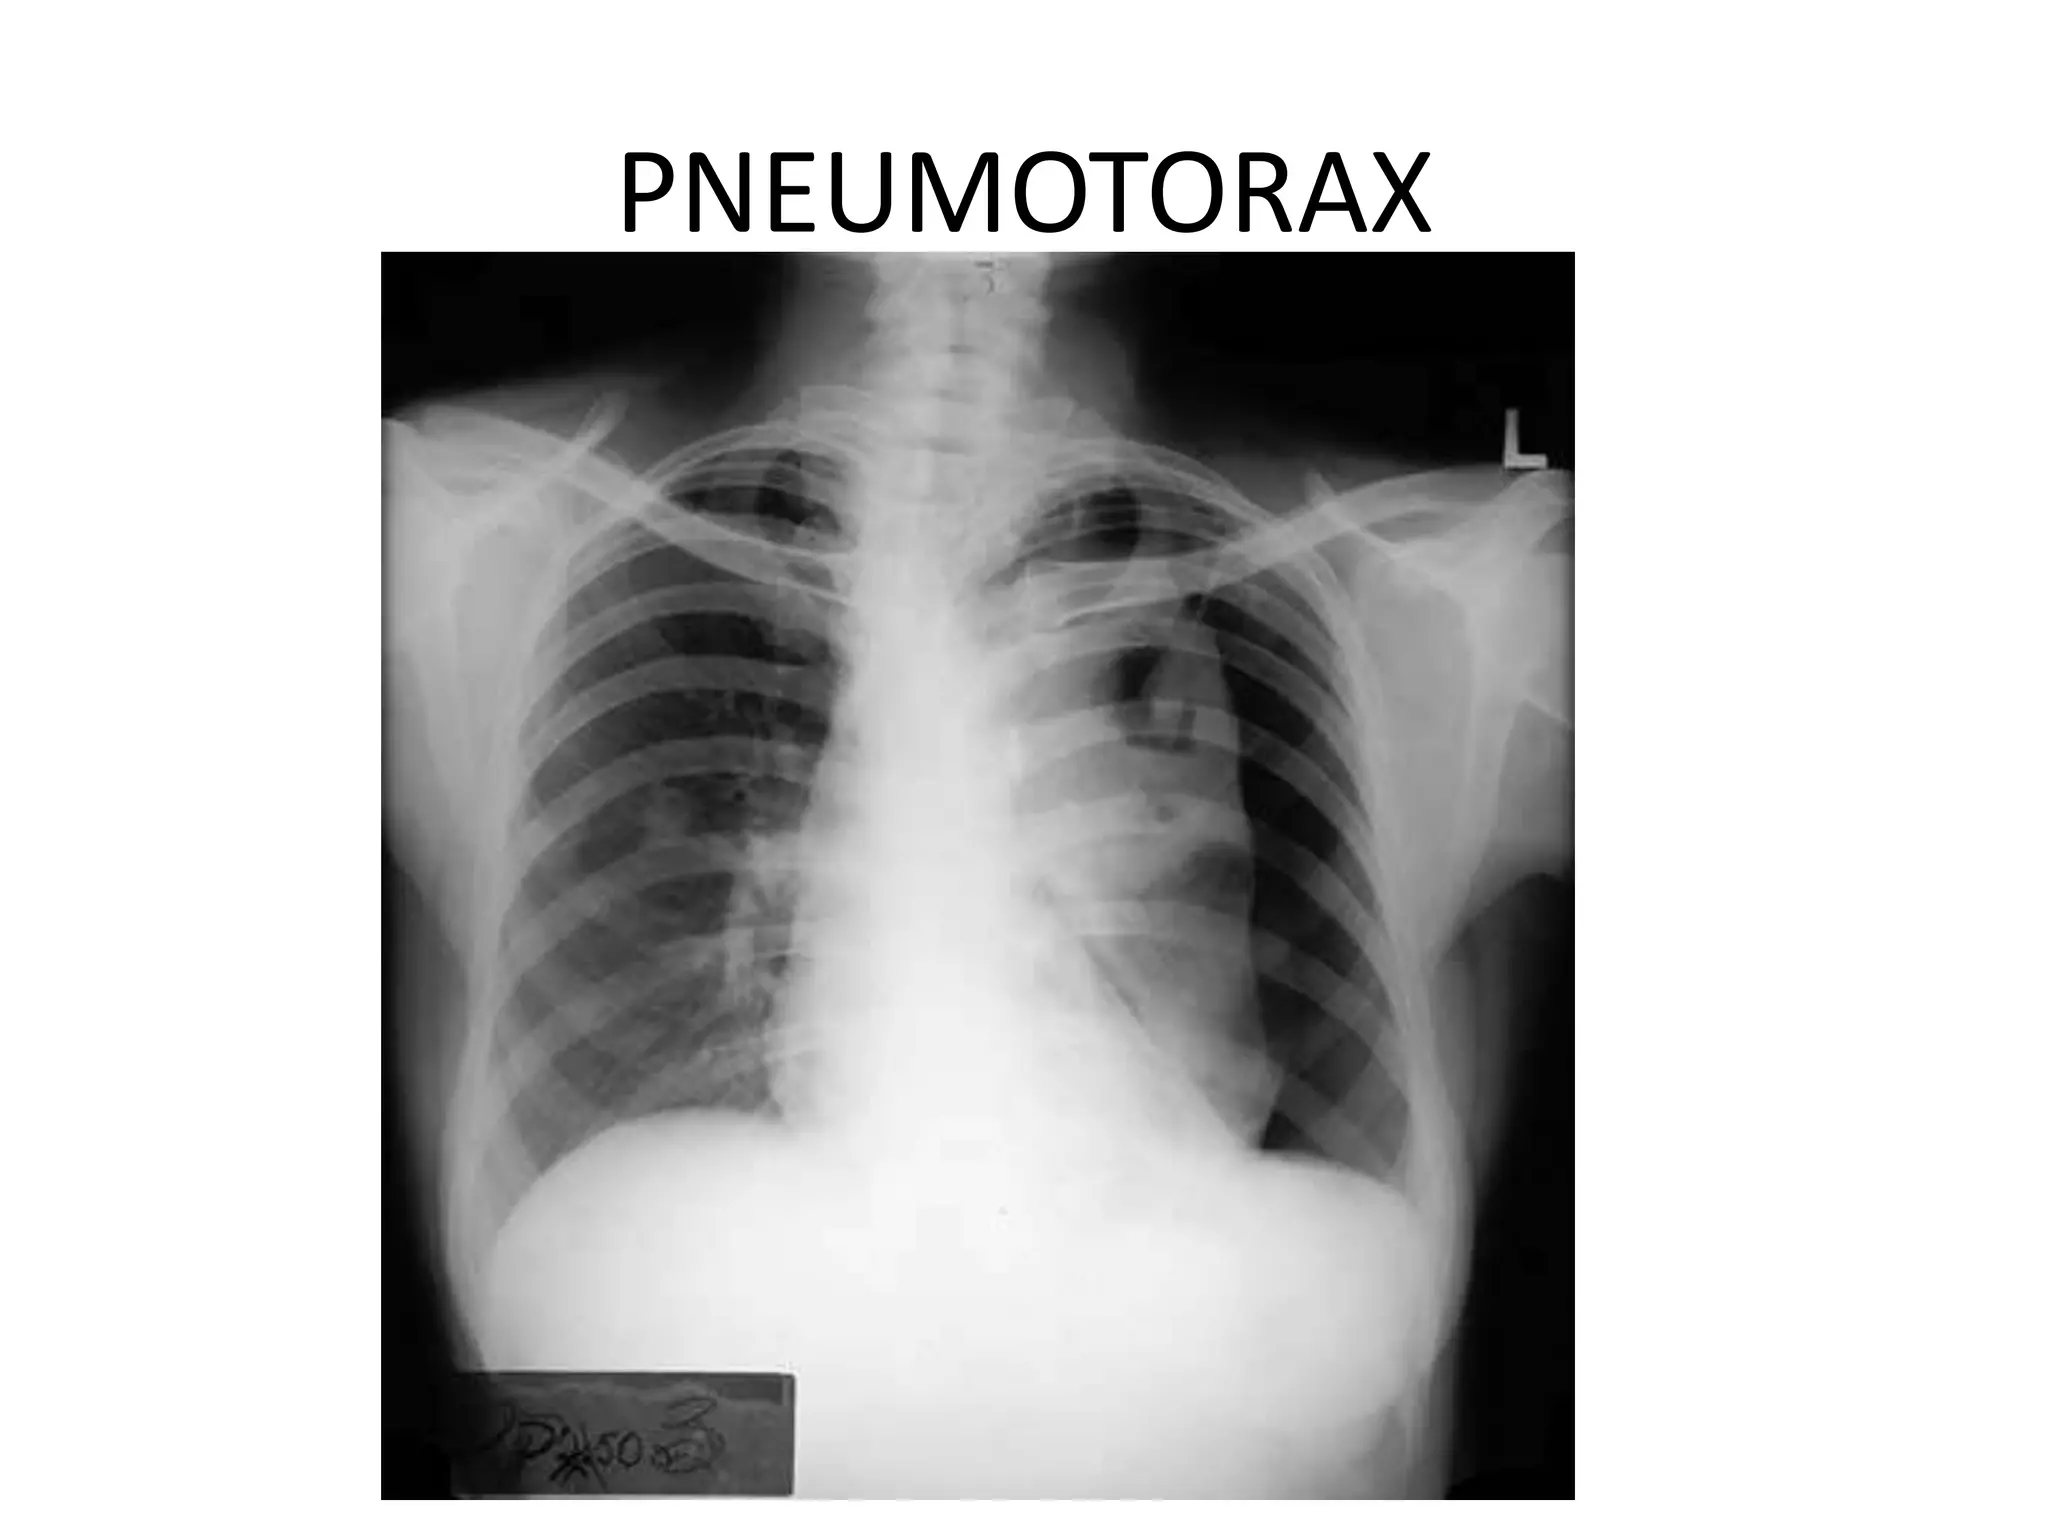

This document provides an overview of key topics in chest x-rays, ECG readings, medical instruments, drugs, and clinical pictures commonly seen in medical orientation classes. It lists various chest x-ray findings like pleural effusion, pneumonia, and pulmonary edema. It also outlines different ECG waves and conditions such as atrial fibrillation, heart blocks, and left ventricular hypertrophy. Common medical instruments like oropharyngeal airways, IV cannulas, and Foley catheters are identified. Examples of anti-tuberculosis therapy, steroids, and clinical pictures including butterfly rash and Cushing's face are briefly covered.